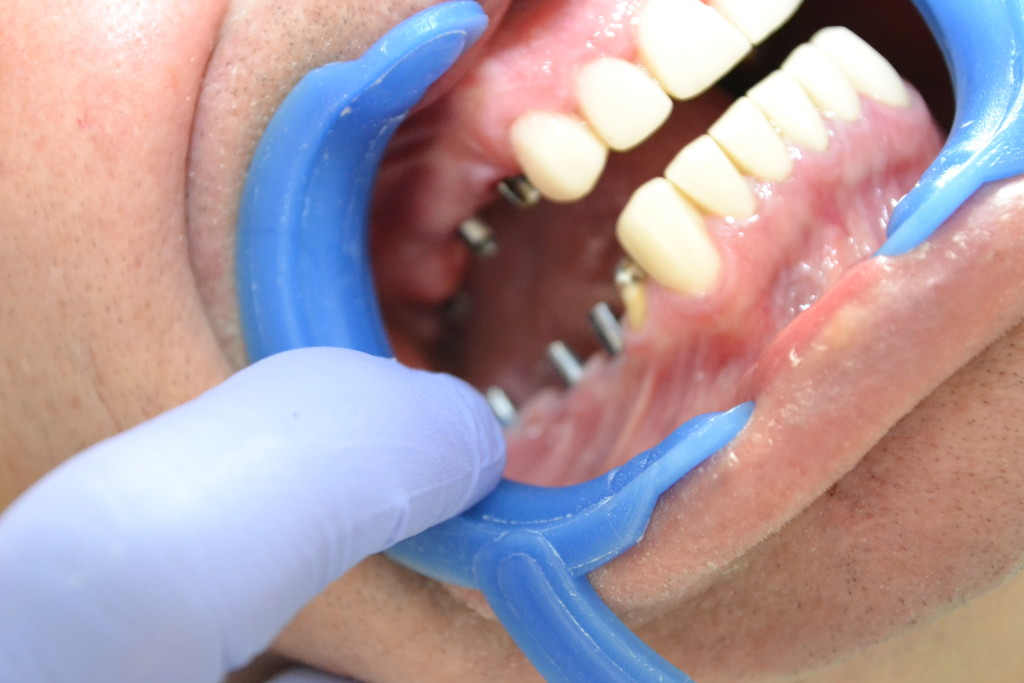

Протезирование двух челюстей безметалловыми керамическими коронками E-max, с опорой на имплантах с циркониевыми абатментами для фронтальных зубов.

- установка имплантов и препарация

- циркониевые абатменты

- прессованная керамика

- безметалловые коронки

- E-max

- отличное прилегание к десне

- вид после протезирования